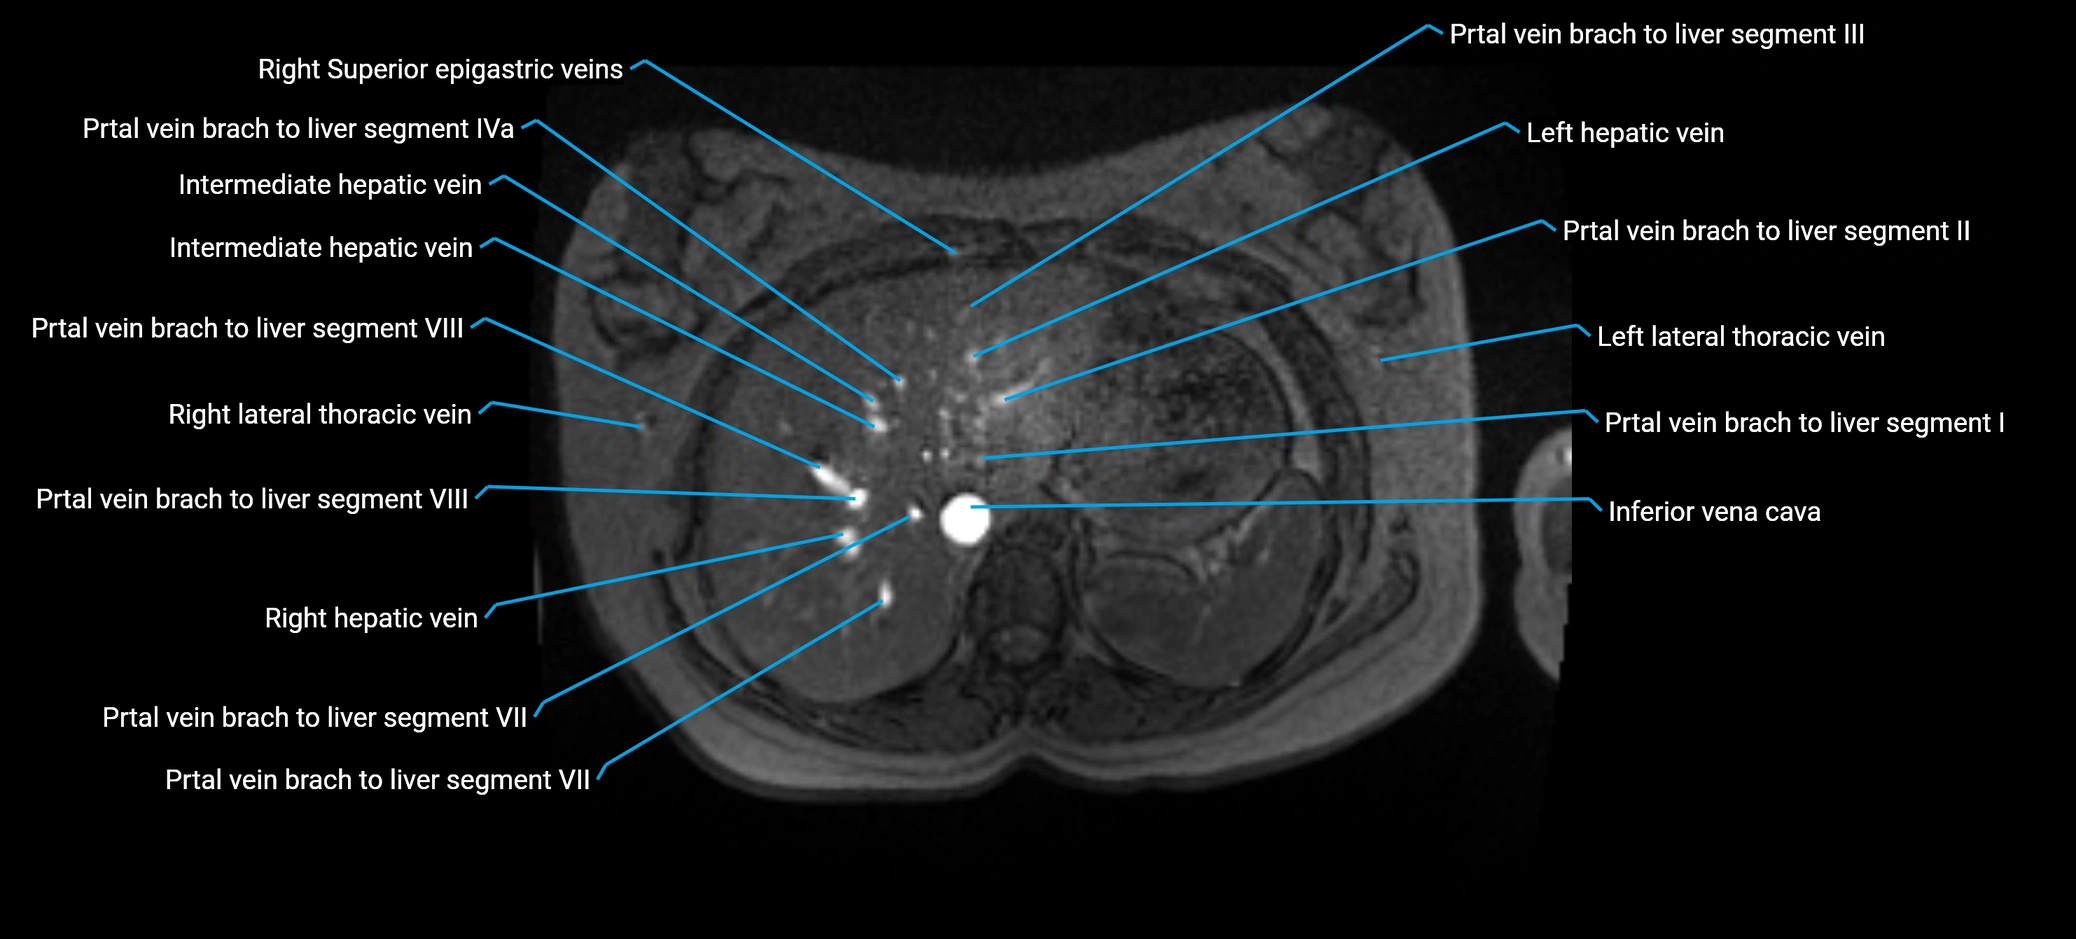

MRI image

image